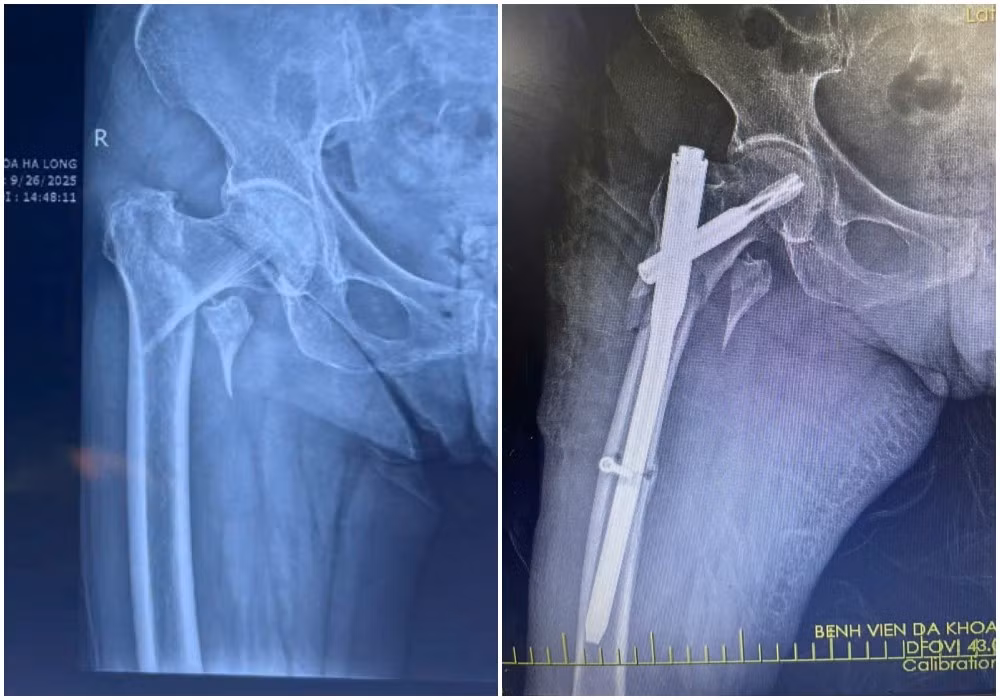

xuong-dui-2.jpg

Hình ảnh X-quang gãy liên mấu chuyển xương đùi trái của bệnh nhân H (88 tuổi) được kíp mổ phẫu thuật kết hợp xương ít xâm lấn - Ảnh BVCC

xuong-dui1.jpg

Hình ảnh X-quang gãy liên mấu chuyển xương đùi phải của bệnh nhân N (87 tuổi) được kíp mổ phẫu thuật kết hợp xương ít xâm lấn - Ảnh BVCC

Kết quả chụp X-quang xác định bệnh nhân bị gãy liên mấu chuyển xương đùi. Với tình trạng tuổi cao, sức yếu, việc vận chuyển bệnh nhân hạn chế, tiềm ẩn nguy cơ làm vị trí gãy thêm trầm trọng.

Kíp mổ do bác sĩ CKII Loan Tám Bảy, Phó khoa Chấn thương chỉnh hình phụ trách phối hợp cùng các bác sĩ Bệnh viện Đa khoa Hạ Long thực hiện phẫu thuật kết hợp xương gãy liên mấu chuyển xương đùi bằng phương pháp ít xâm lấn.

Qua đường rạch da nhỏ khoảng 3-5cm, phẫu thuật viên nắn chỉnh xương gãy về vị trí giải phẫu, sau đó cố định bằng đinh nội tủy PFNA dưới màn hình tăng sáng (C-arm).